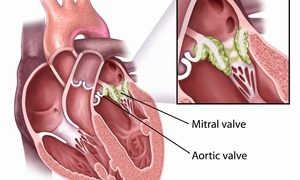

犬の心臓弁膜の疾患(acquired heart diseases)家畜の後天性心疾患については、各種動物でかなりの発生をみていますが、ここではその主なものについて記載します。犬の心臓弁膜の疾患(valvular heart disease...